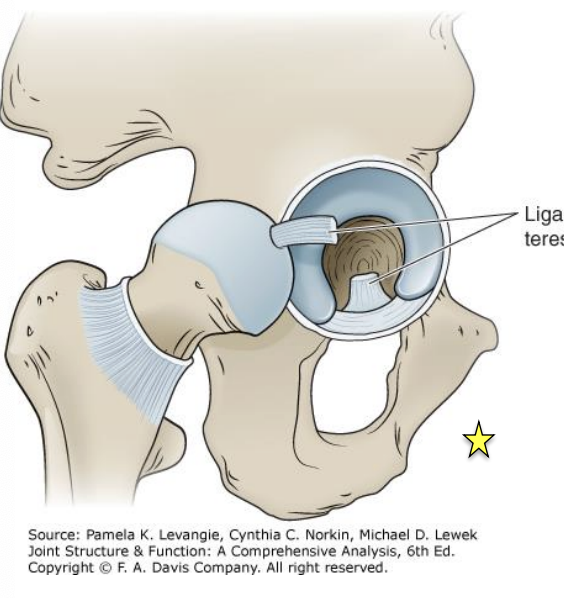

ligamentum teres

O&I: from acetabular notch to the fovea

intra-articular but extrasynovial

conduit for secondary blood supply to the femoral head

recent studies show it provides some stability

-limits hip IR and ER (when hip is >90 deg flexion)